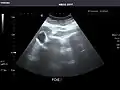

Renal ultrasonography

Ultrasound scan of a kidney (right side)

Ultrasonography of the kidneys is essential in the diagnosis and management of kidney-related diseases. The kidneys are easily examined, and most pathological changes in the kidneys are distinguishable with ultrasound.[7]

Kidneys: Right and left kidneys measure 11.5 cm and 12 cm in length respectively. No hydronephrosis. Small left lower pole kidney cyst.